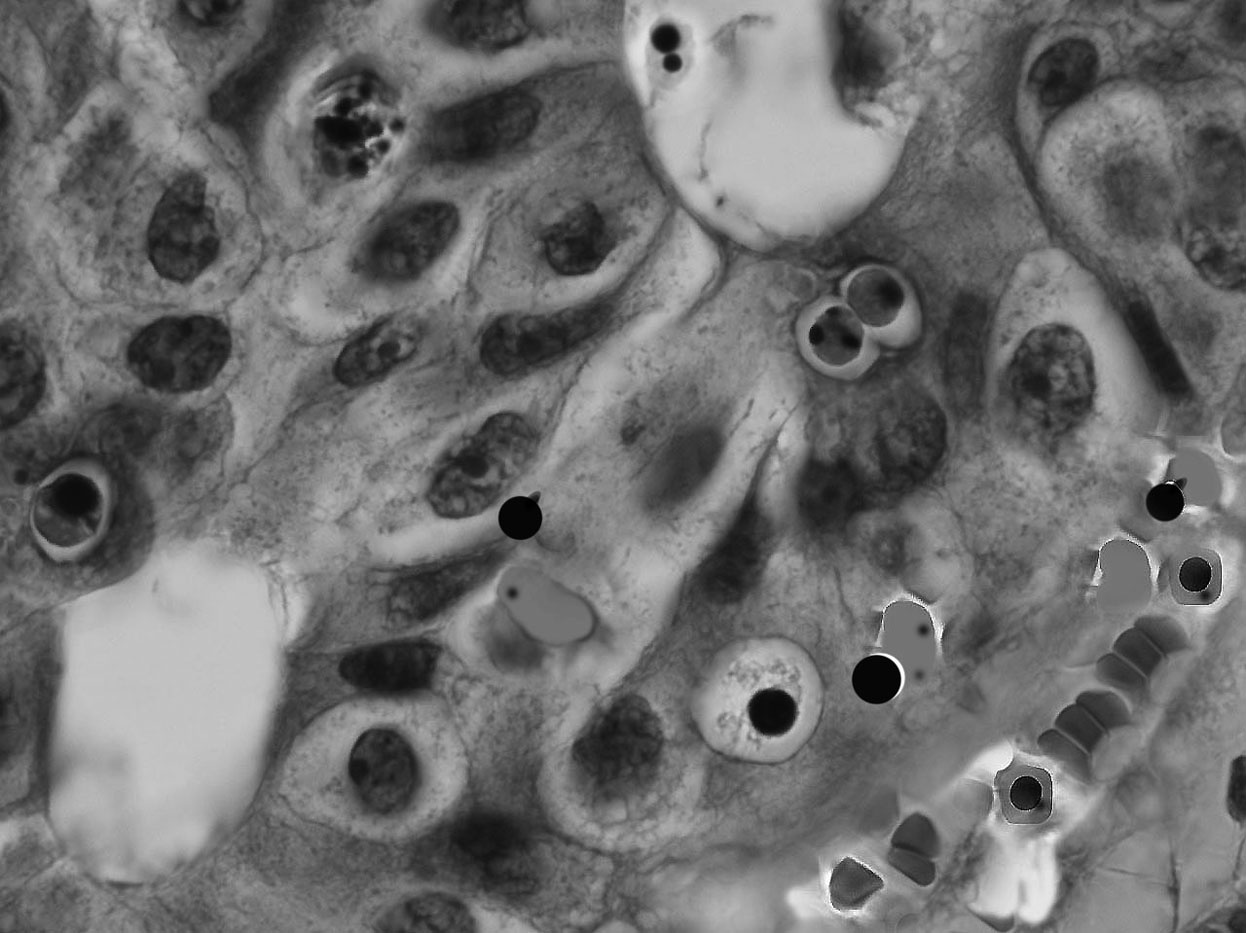

Figure legend. Human carcinoma. In the left upper corner is a large cancer cell in apoptosis. The rest of the field consists of enucleated and degenerating nucleated red cells in tumor capillaries. Enucleating erythroblasts gives rise to near naked nuclei (Nanus) of compacted chromatin (Oncotropic stem cells) and acidophilic bodies (Erythroid plastids). Apoptoic nuclear segmentation is present in erythroid cells. (HE.oi.10x100).